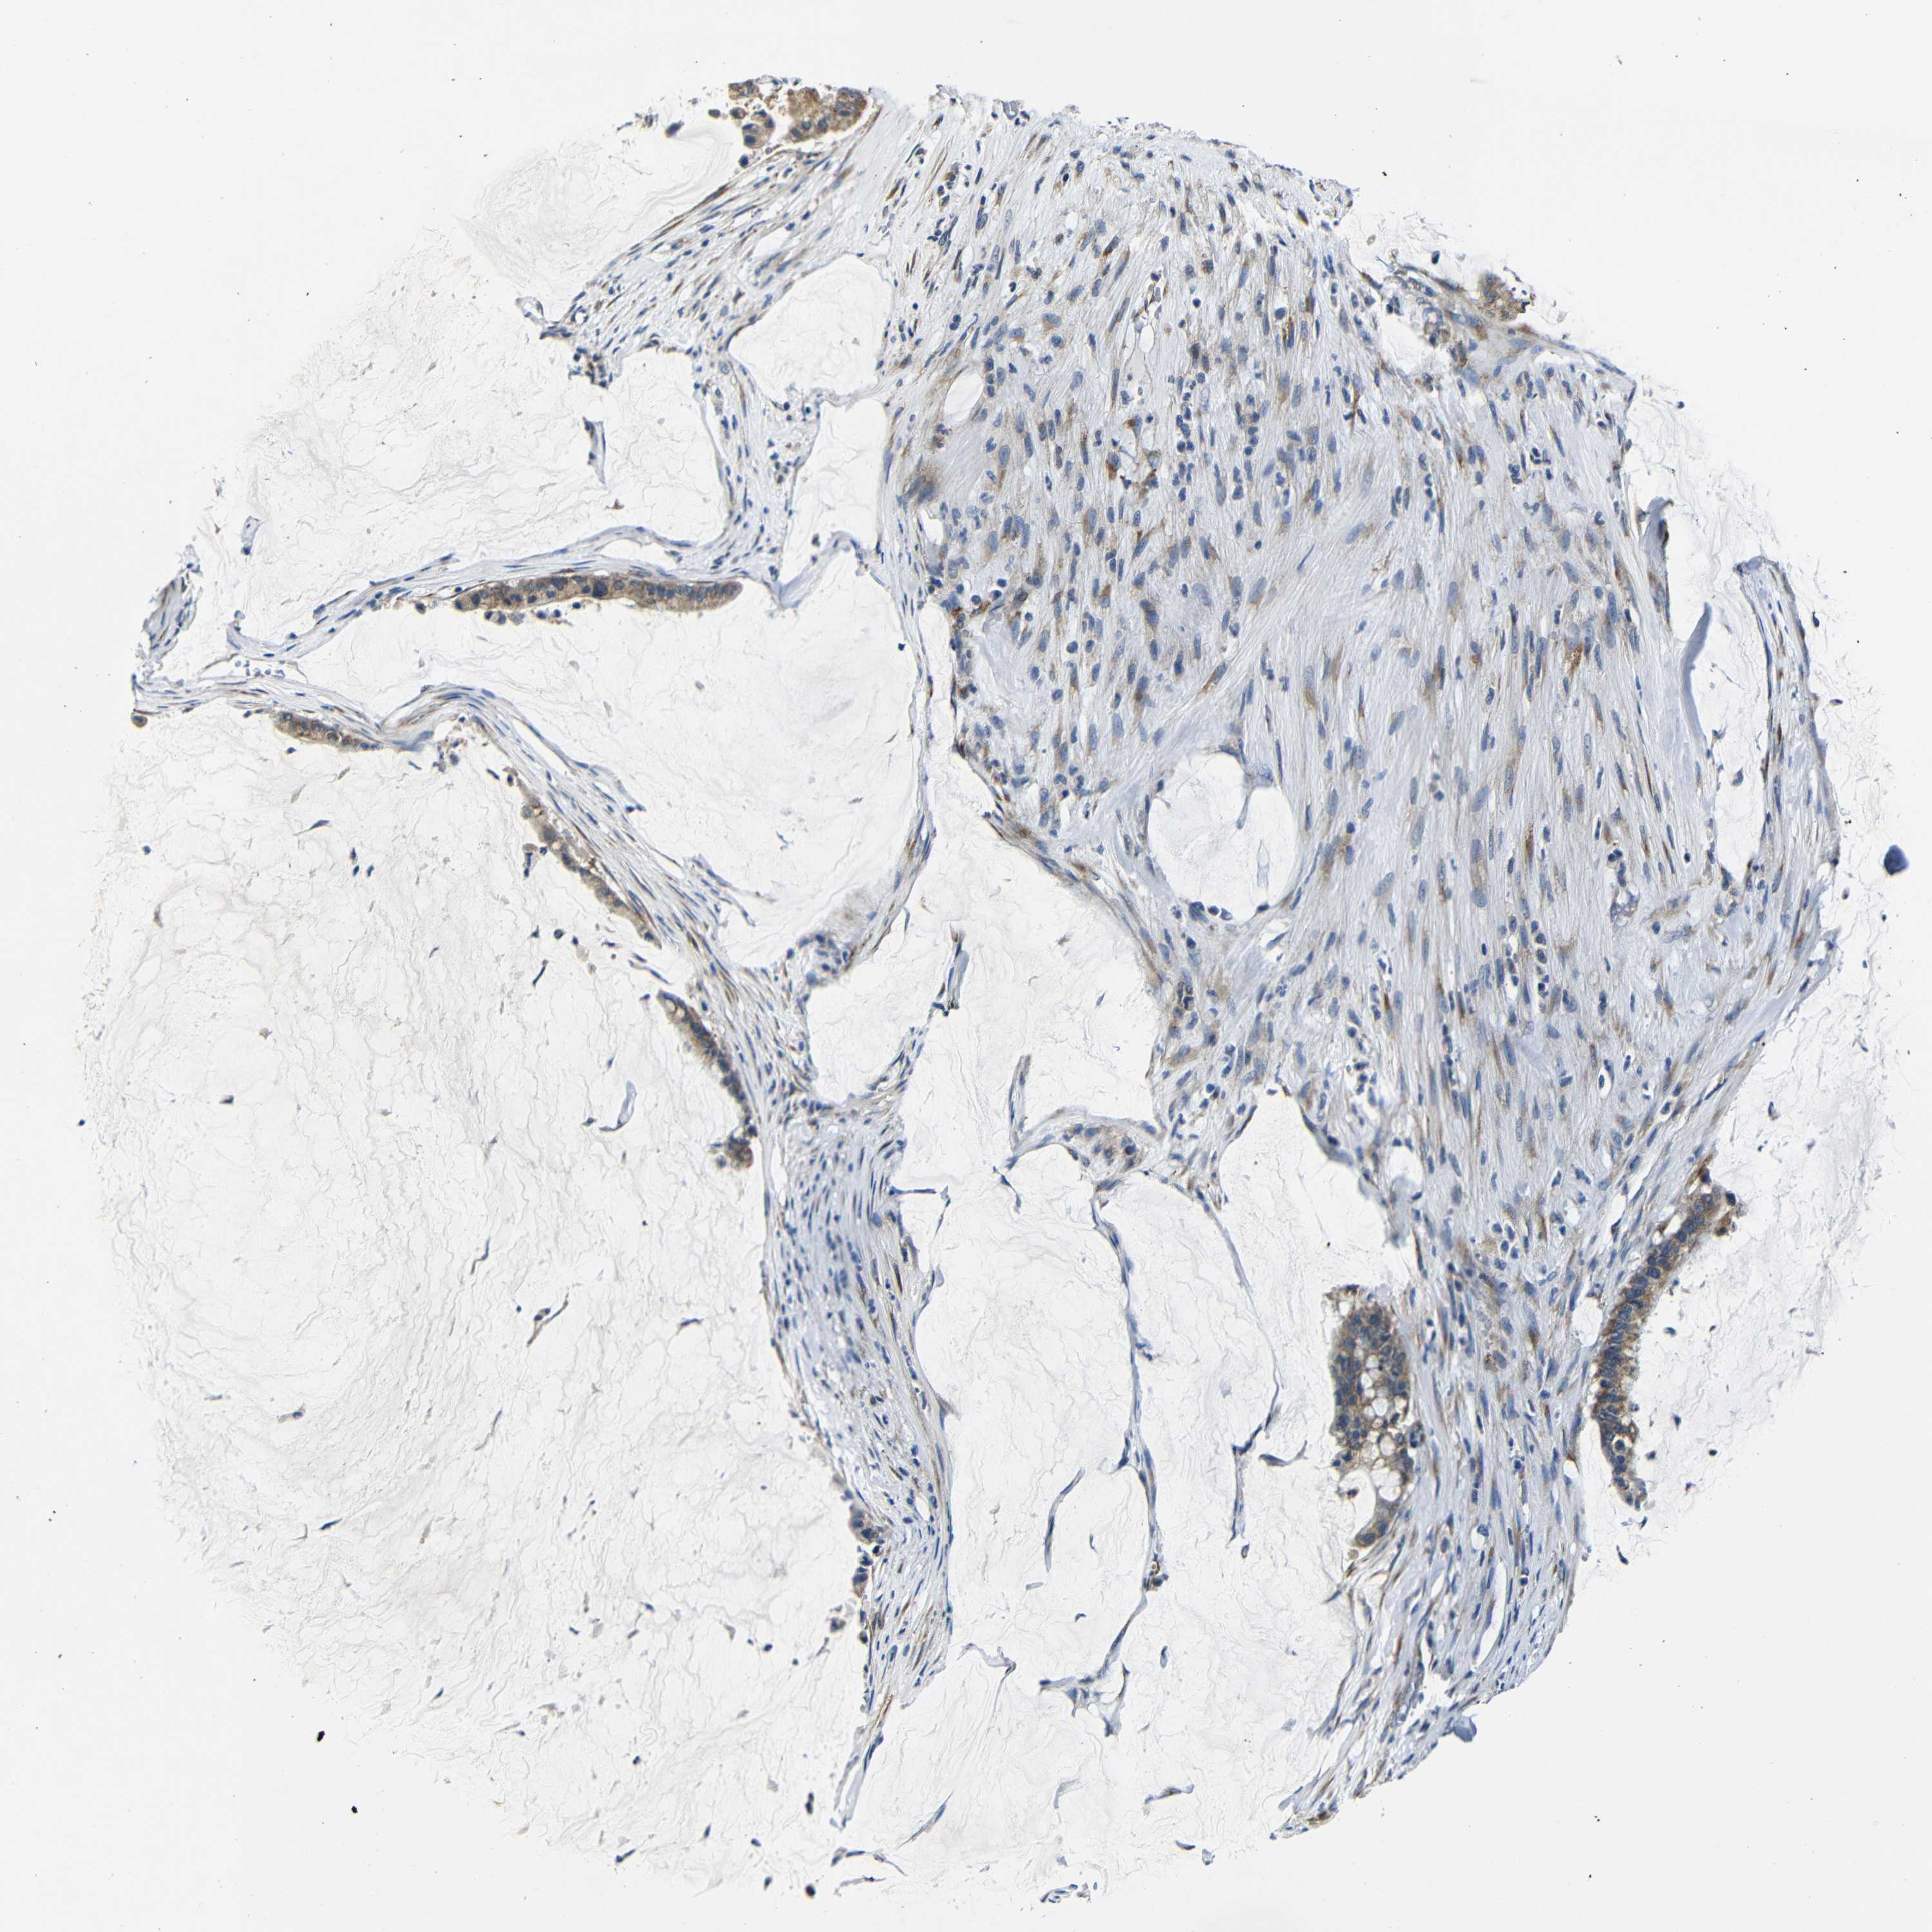

PANCREATIC CANCER - Protein expressioni

A mouse-over function shows sample information and annotation data. Click on an image to view it in a full screen mode. Samples can be filtered based on level of antibody staining by selecting one or several of the following categories: high, medium, low and not detected. The assay and annotation is described here.

Note that samples used for immunohistochemistry by the Human Protein Atlas do not correspond to samples in the TCGA dataset.

Antibody stainingi

Antibody staining in the annotated cell types in the current human tissue is reported as not detected, low, medium, or high, based on conventional immunohistochemistry profiling in selected tissues. This score is based on the combination of the staining intensity and fraction of stained cells.

Each image is clickable and will lead to virtual microscopy that enables deeper exploration of all samples and also displays staining intensity scores, fraction scores and subcellular localization as well as patient and tissue information for each sample.

Antibody HPA013329

Antibody HPA026829

Staining

High

Medium

Low

Not detected

Intensity

Strong

Moderate

Weak

Negative

Quantity

>75%

75%-25%

<25%

None

Location

Nuclear

Cytoplasmic/membranous

Cytoplasmic/membranous,nuclear

Adenocarcinoma, NOS